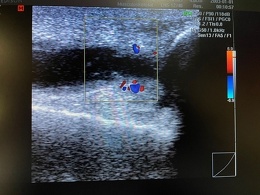

デイサービスご利用者様の膝のエコー写真です。

機能訓練時に膝の疼痛を訴えられたため、エコーにて観察。

膝外側に関節水腫、内側に脂肪種様物質、膝窩(膝の裏側)にBaker嚢腫を確認しました。

1週間後には膝外側の水腫は消失しておりましたが、脂肪種、Baker嚢腫は変わらないので医療機関の受診をお勧めしました。